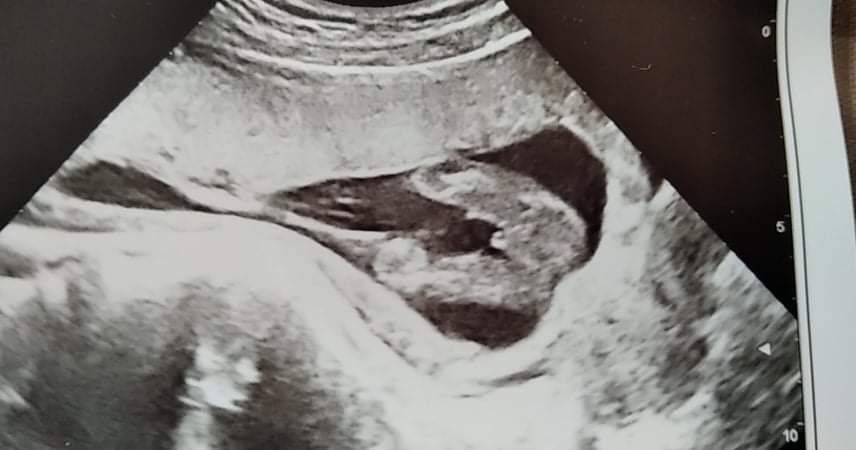

Според генеколога: това мду крачетата не е пъпна връв